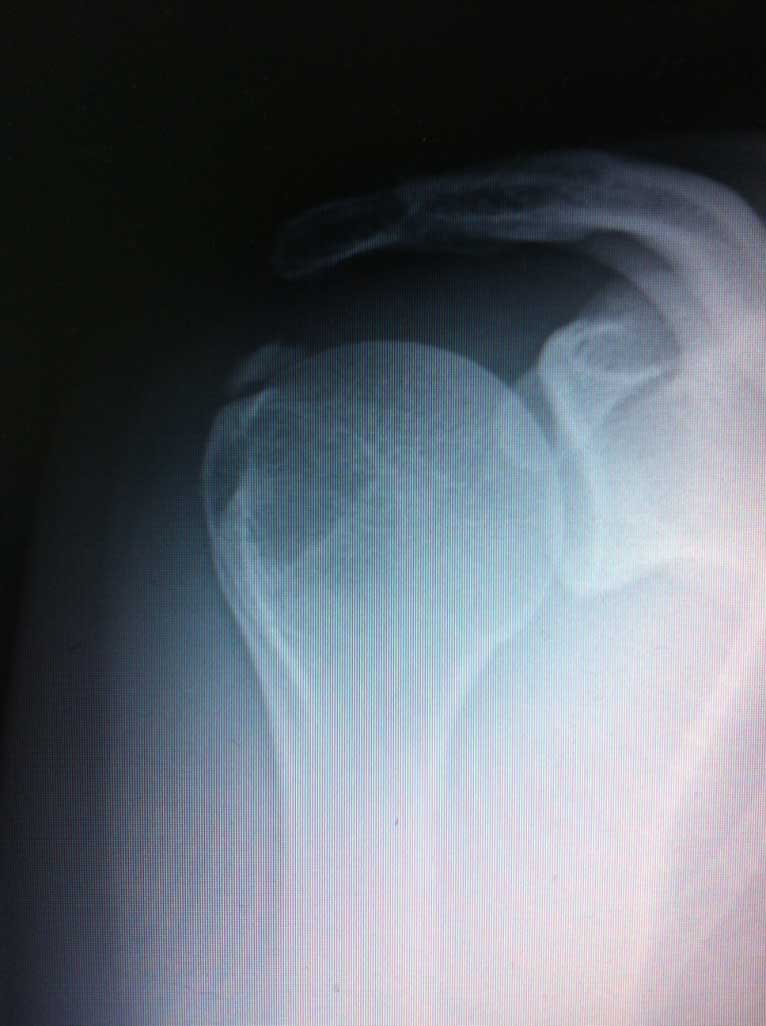

Das eigentliche Schultergelenk besteht aus 2 knöchernen Partnern, dem Oberarmkopf und der Gelenkpfanne, welche ein Teil des Schulterblattes ist. Dank der sehr flachen und eher kleinen Pfanne und wesentlich grösserem Kopf ermöglich die knöcherne Zusammensetzung des Gelenkes ein sehr grosses Bewegungsausmaß desselben.

Sowohl der Oberarmkopf als auch die Gelenkpfanne sind im Bereich der Gelenkfläche mit einem hyalinen Gelenkknorpel überzogen.

Eine Unfall- oder Anlagebedingte (oder kombinierte) Instabilität der Schulter führt zum Auskugeln (luxieren) des Oberarmkopfes aus der kleinen flachen Gelenkpfanne.